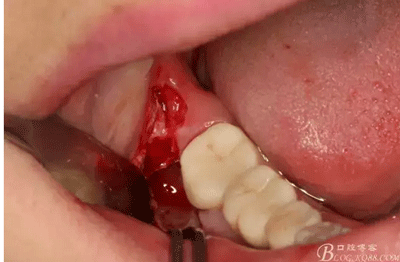

圖4. 47全瓷牙的遠(yuǎn)中科探及深的盲袋。